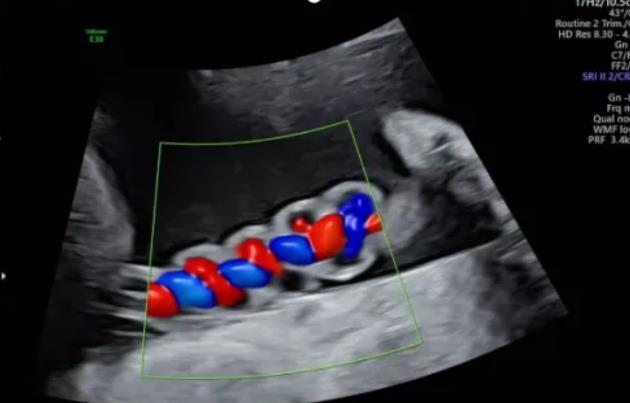

漯河市中醫(yī)院健康科普:超聲檢查之臍帶螺旋

臍帶螺旋指數(shù)(umblical coiling index UCI)指每1cm臍帶螺旋的周數(shù),等于臍帶的完全扭轉(zhuǎn)數(shù)÷臍帶長度(cm);為臍血管扭轉(zhuǎn)的診斷提出了量化標(biāo)準(zhǔn),它能反映螺旋的周數(shù),更重要的是能夠反映螺旋的疏密度,是簡單、客觀、量化臍帶血管螺旋的指標(biāo)。

正常范圍及意義:正常情況下,臍血管生理性扭轉(zhuǎn)約6~11螺旋,即臍帶約5cm形成1個完全的螺旋圈,UCI<0.07考慮為螺旋過松;UCI﹥0.36考慮為螺旋過緊。理論上講過松和過緊均會影響胎兒發(fā)育。

聲像圖特征:臍動脈表現(xiàn)為過度螺旋,臍血管變細,縱切面呈“麻花狀”,橫切面呈“鼠眼狀”;

聲像圖特征:胎兒臍帶縱切面示血管呈平行排列,螺旋稀少,彩色多普勒血流成像示臍帶血管內(nèi)充滿的紅藍血流呈平行排列,麻花狀螺旋消失。